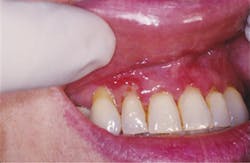

Figure 1 depicts the palatal lingual gingiva with extreme redness. Figure 2 depicts the gingival areas in a patient with MMP with epithelial stripping around the margin of #7. Figure 3 depicts the scarring of the eye and symblepharon/entropion and adhesion of the eye.

Figure 3: Scarring of the eye. Courtesy of Dr. T.D. Rees.

Ocular pemphigoid, as the name suggests, involves the eyes. The prime area that is most affected is the oral cavity but sometimes the first indication of MMP may be the eyes, which is then followed by oral tissue inflammation. Patients may complain of redness, tearing, burning, decreased vision, and/or a foreign body sensation. OCP may progress at any stage of disease.

The treatment of ocular pemphigoid has improved over the years and is being more recognized by health-care providers. Early treatment is needed before significant scarring occurs. In prior years, the patient could suffer severe damage to the eyes and often suffer vision loss because of the extensive scarring.